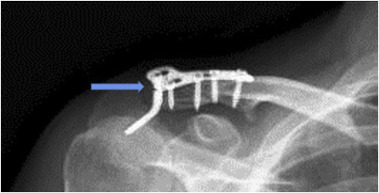

Fig. 2

Fig. 2.

Anteroposterior radiograph of a fully united Neer type 2 distal clavicle fracture with a four-hole hook plate failure (blue arrow) after 6 months which required implant removal (For interpretation of the references to colour in this figure legend, the reader is referred to the web version of this article).

There were no intraoperative complications. Radiographs showed union on the 3rd postoperative month in 13 patients, and on the 4th month in 3 patients. Three patients developed superficial skin infections after the operation, and they healed uneventfully with wound care. Radiological evaluation revealed a radiolucent area, located where the hook part touched the acromion, in 4 patients on the 3rd month, and in 6 patients on the 4th month. This was accepted as acromial osteolysis (Fig. 1 ). The plates were removed in all these 10 patients (62%) within the following month. One patient had a plate fracture on the 6th month (Fig. 2 ). During the plate removal, sufficient union was seen, therefore an additional procedure was not found to be necessary. Seven patients (42%) developed symptoms of subacromial impingement syndrome (SIS) after an average period of 2.5 months. Diagnosis was confirmed with a positive Neer test. Mean modified UCLA score at the final follow up was 32.75 (range 31–35). Twelve patients (68%) underwent plate removal due to acromial osteolysis, impingement syndrome and implant failure. After removal, the complaints regressed and shoulders' range of motion increased. At the final follow up; mean modified UCLA score was 32.75 (range 31–35). There were no acromioclavicular joint arthrosis in the patients (Table 1 ).